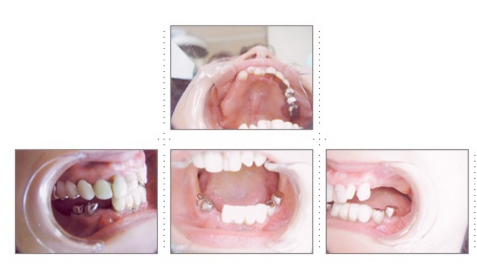

症例1

58才 女性

嘔吐反応が激しく入れ歯を入れると気持ち悪くなってしまうと、インプラント希望で来院されました。

上顎左右奥に4本ずつ計8本のインプラント埋入。下顎左右奥に3本ずつ計6本のインプラント埋入上下顎とも全体的にセラミックを使用した冠をセット。